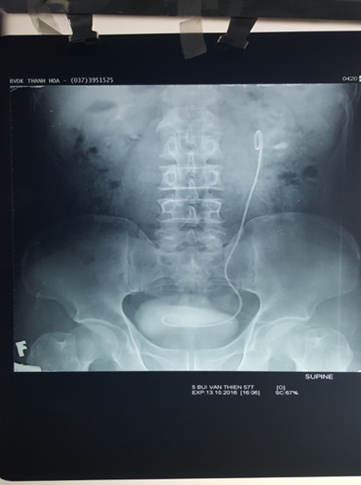

Bệnh do ký sinh trùng là một bệnh thường gặp và phổ biến khắp thế

BS . Nguyễn Thị Thanh Hương Khoa Nội Tiêu Hóa Trong những năm